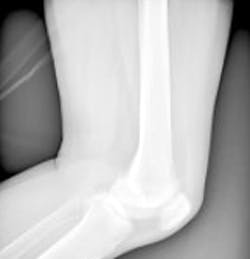

The team is making a compact Magnetic Resonance Imaging (MRI) system for hospitals that could improve the way that joints including knees and elbows are scanned. The system could help doctors to make more informed decisions about surgery, which could improve outcomes and recovery times for patients.

The system will be designed specifically to image knees, but the approach could also be used to image a wide variety of body parts.